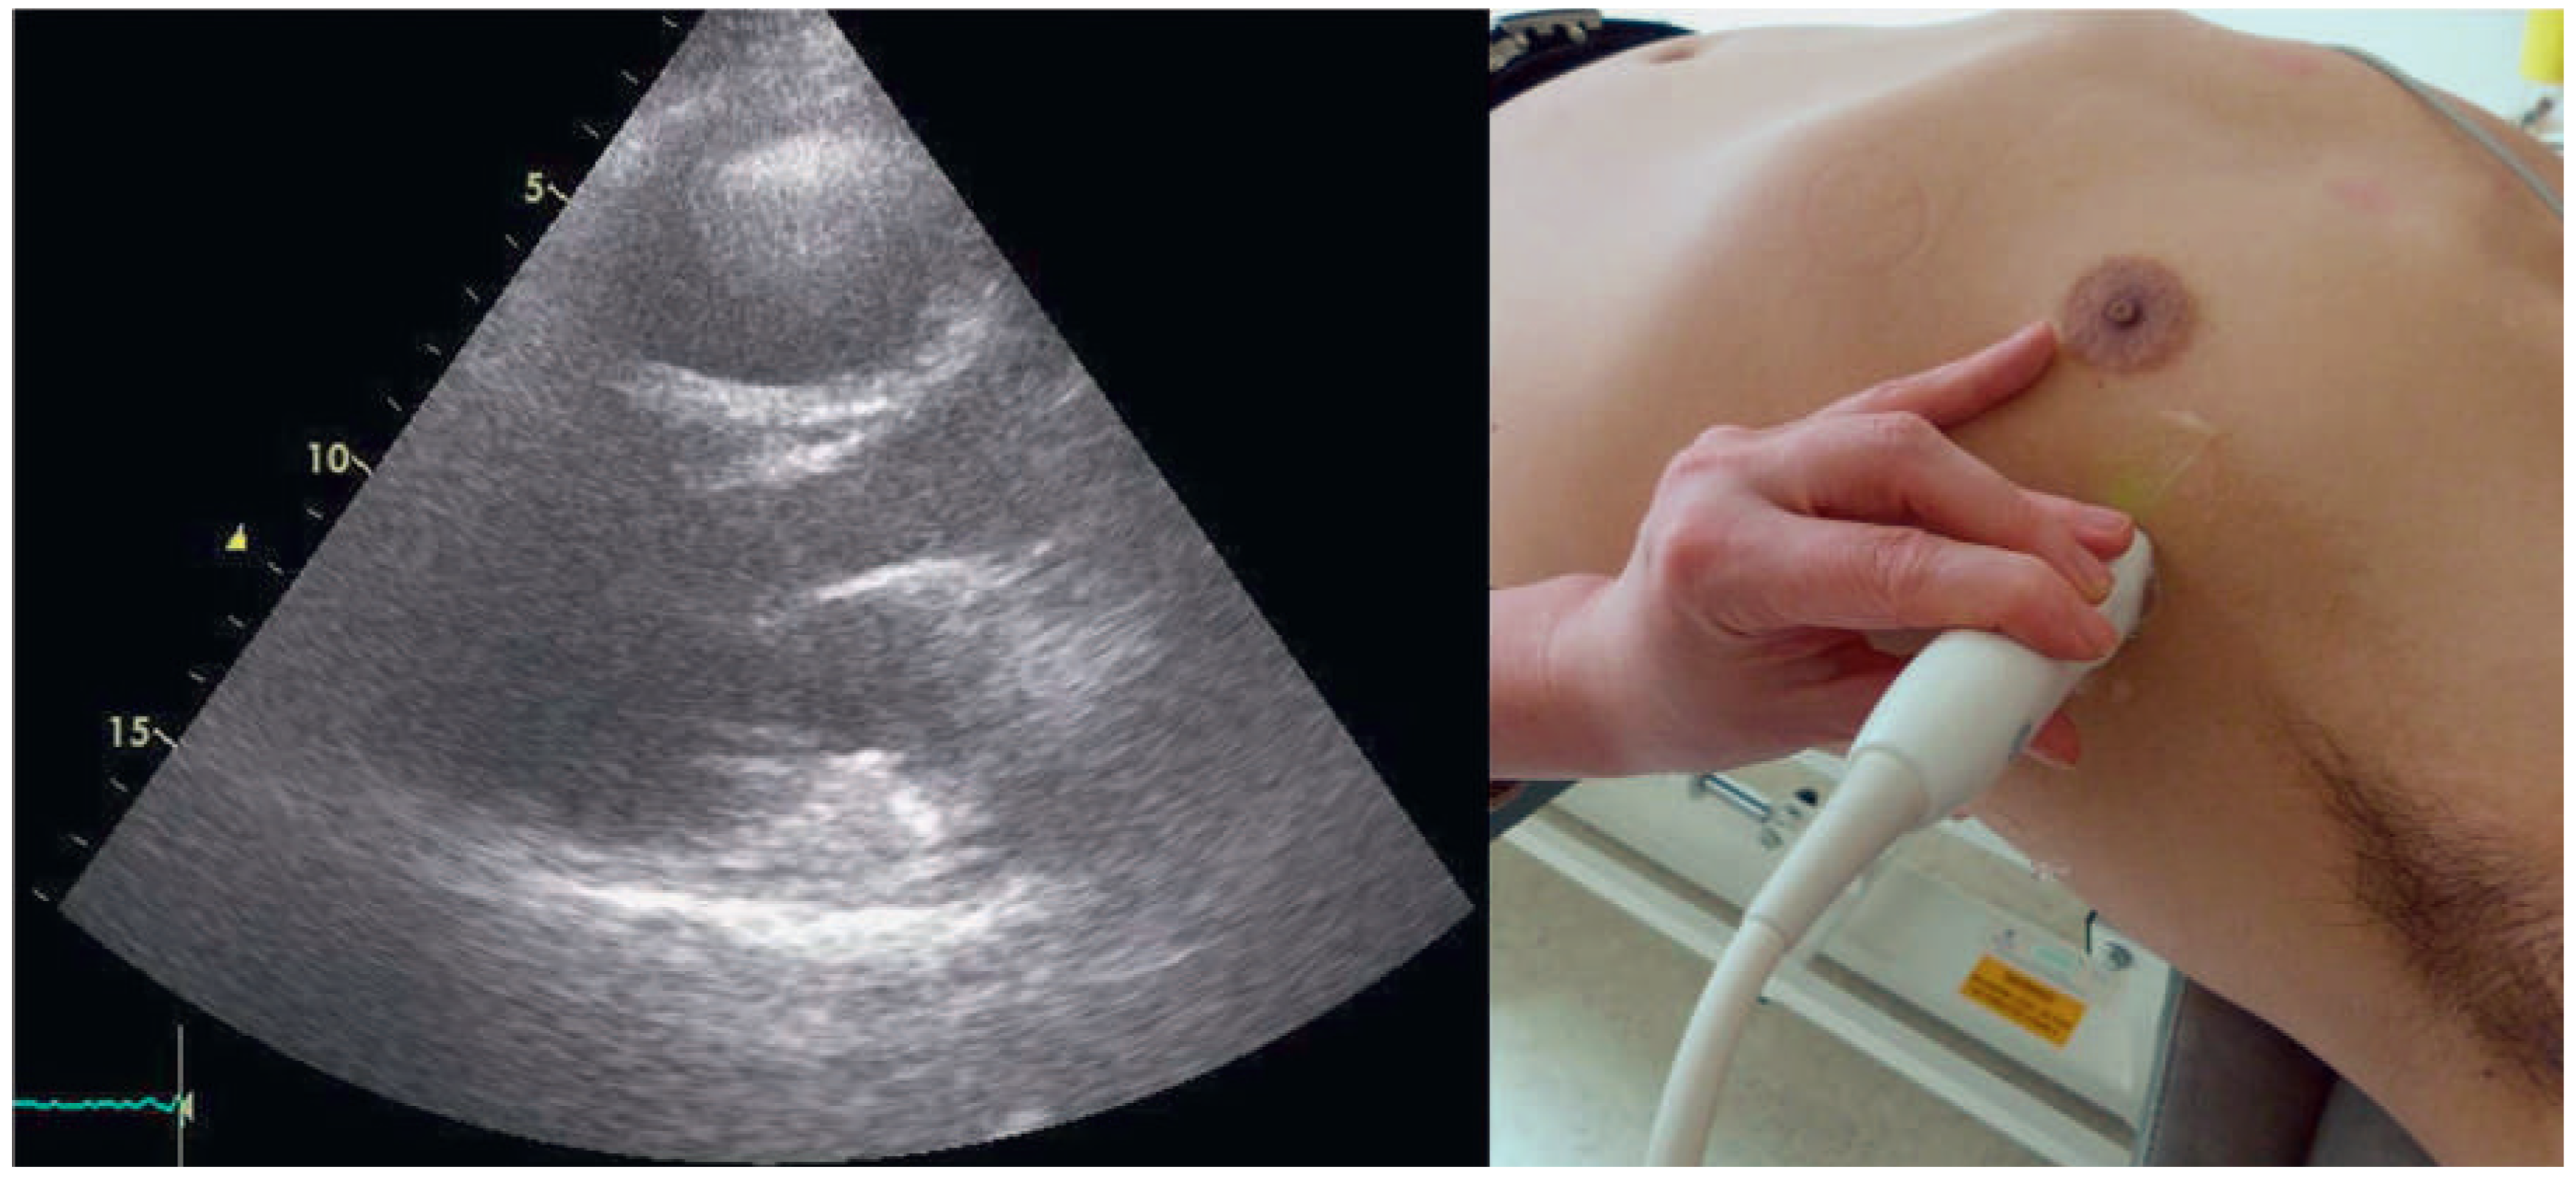

A 57-year-old male presented to the medical outpatient department with typical angina pectoris Canadian Cardiovascular Society (CCS) class II and dyspnoea on exertion during the previous weeks. Additionally he had retrosternal pain at rest and dyspnoea during the previous night. The patient had a a history of untreated arterial hypertension. On initial workup, the patient was in a stable cardiovascular condition with an office blood pressure of 150/88 mm Hg, and the cardiac examination was unremarkable. Blood tests revealed serially negative high-sensitivity troponins. Glycated haemoglobin was 6.4%, consistent with prediabetes, and lowdensity lipoprotein cholesterol was 2.5 mmol/l. An electrocardiogram (ECG) showed sinus rhythm, right axis deviation, signs of an incomplete right bundle-branch block with rR’ morphology in leads V1 to V4, and lateral displacement of the transition zone in the precordial leads, but no signs of acute ischaemia (Figure 1). On echocardiography, the image acquisition was difficult with a typical long axis view acquired in the fifth intercostal space in the midaxillary line (Figure 2) and apical views acquired from a posterolateral window (Figure 3). Computed tomography angiography (CTA) of the heart showed that the entire heart was displaced leftwards into the left hemithorax. Also evident was a lingula of lung tissue interposed between the aorta and the pulmonary artery indicating a congenitally absent pericardium (Figure 4). Additionally, the CT scan revealed coronary artery disease with soft plaques and >70% stenoses of the left anterior descending artery (LAD), the left circumflex artery (50%–70% stenosis) and the first marginal branch (>70% stenosis). Considering the diagnosis of a congenitally absent pericardium, the ECG was repeated, with leads V7–V9, showing a normal R-progression from V4 to V9 (Figure 5). Coronary angiography with primary stenting of a 95%–99% stenosis of the LAD artery and a 75%–95% stenosis of the first marginal branch resulted in complete resolution of symptoms.

Figure 3. Apical four-chamber view derived from a posterolateral window.